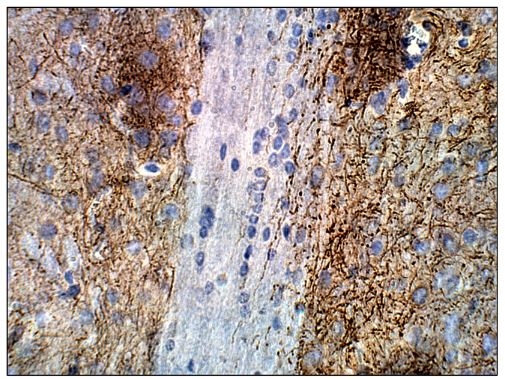

IHC-P analysis of mouse brain tissue using GTX14777 Adenylate cyclase 2 antibody.

Dilution : 1:50